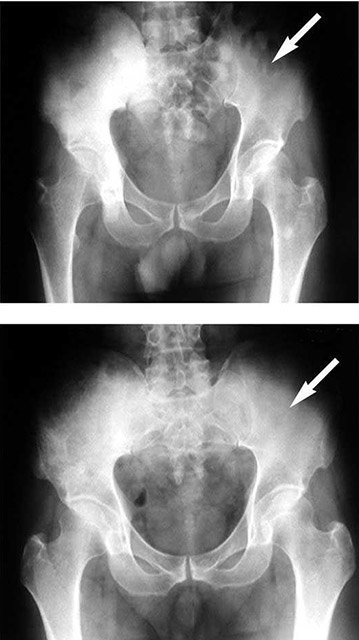

精神科医塩入俊樹氏前回お話しした「報酬系」の神経回路に関係する主な脳部位を示したものが図です。「報酬系」は、食行動や性行為などの本能的行動を快感として感じることで、生命を維持するためのこれらの行...